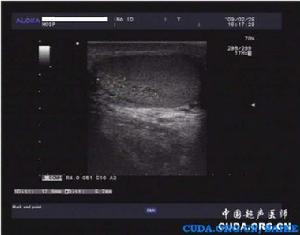

睪丸實質內表現出大小不等的無回聲區,占據整個睪丸的1/3或2/3,主要分布在睪丸縱膈鄰近區域,無回聲區域內無血流色彩充填,鄰近睪丸組織血流色彩正常。白膜呈正常組織回聲,不受累、不均厚。